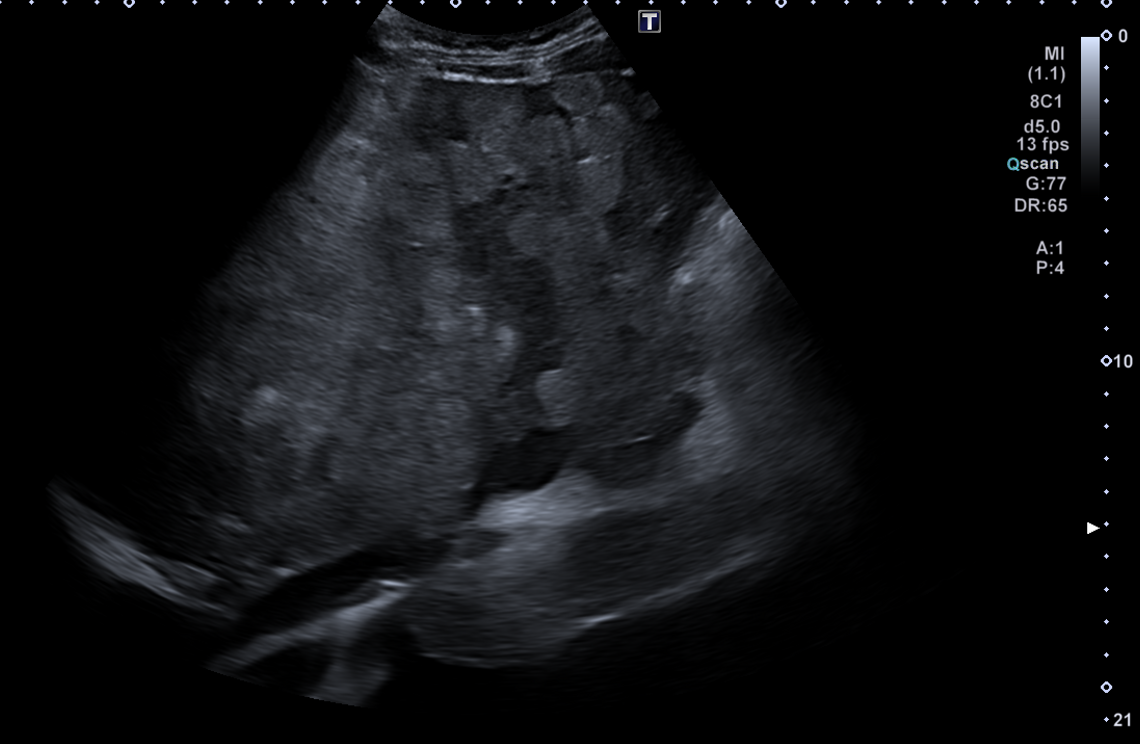

Descripción de los hallazgos ecográficos y las imágenes más relevantes para la resolución del caso

En ecografía en Centro de Salud: La práctica totalidad del parénquima hepático se encuentra sustituida por múltiples lesiones sólidas nodulares hiperecoicas, de predominio en el lóbulo hepático derecho, donde presentan tendencia a la confluencia y conforman una masa que alcanza los 13 cm de diámetro máximo. La vena porta es permeable y ectásica, con esplenomegalia. Ambos son signos de hipertensión portal.

Ante estos hallazgos se deriva al paciente a Urgencias.